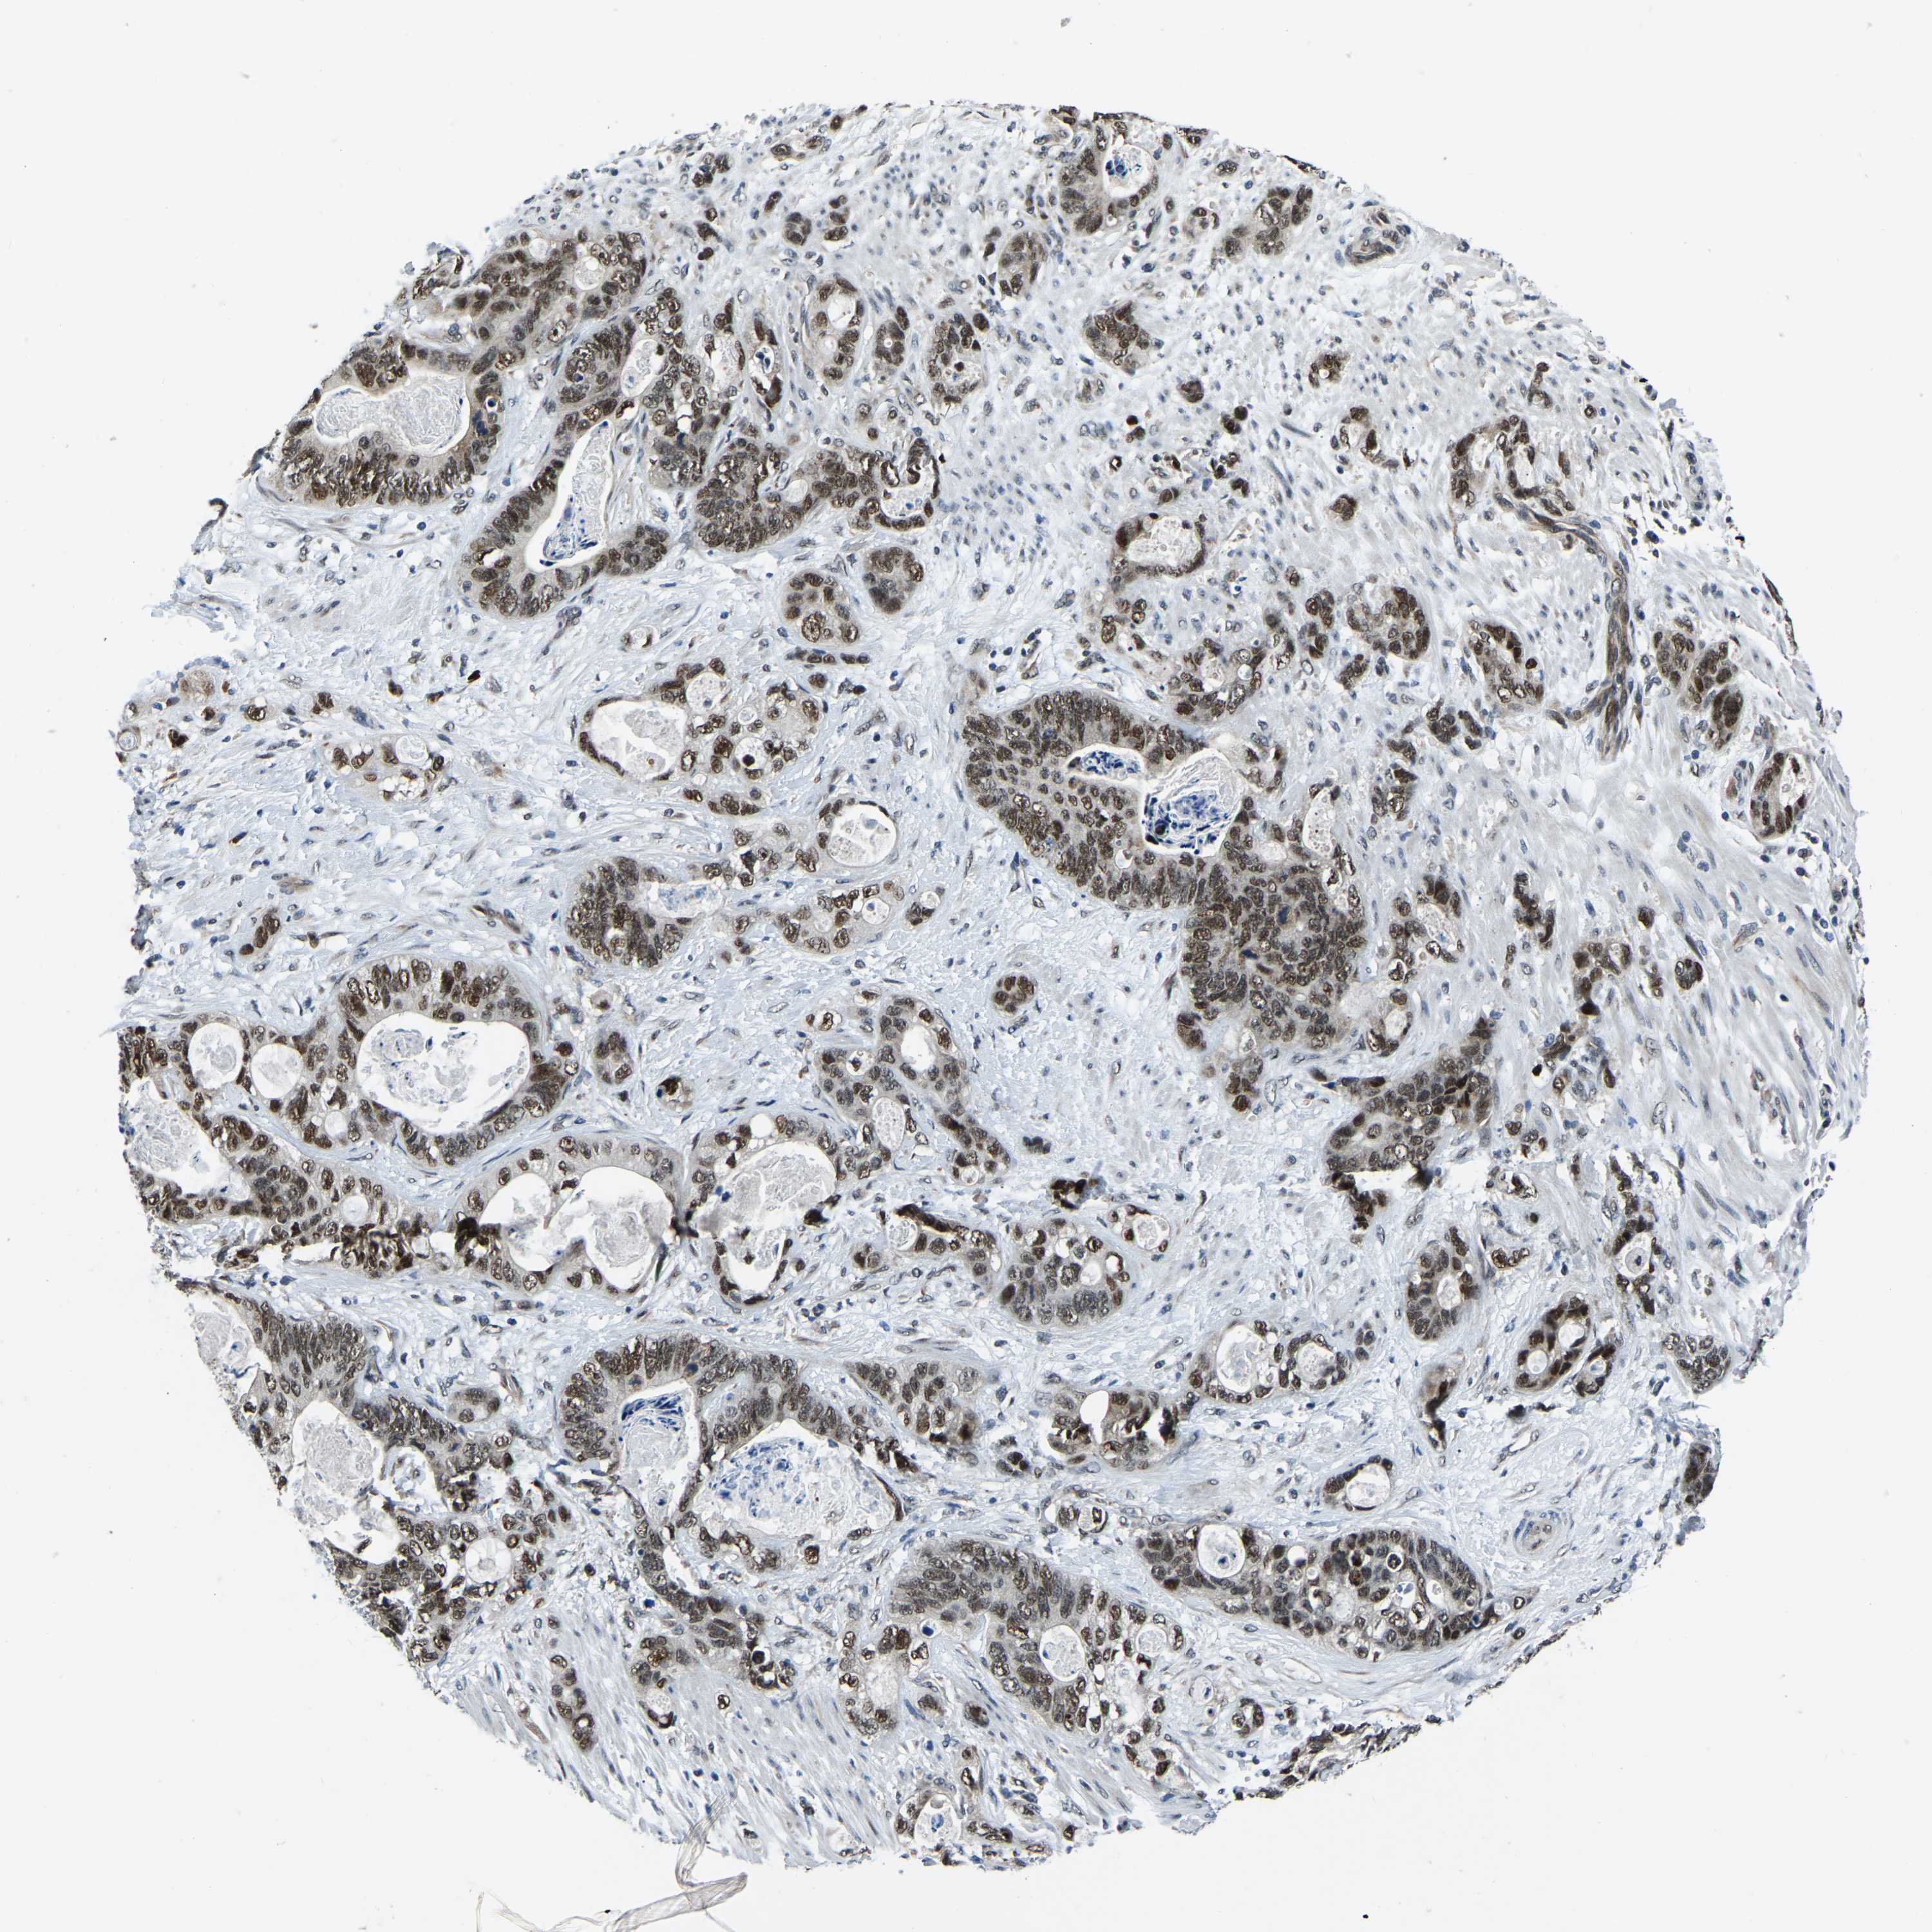

STOMACH CANCER - Protein expressioni

A mouse-over function shows sample information and annotation data. Click on an image to view it in a full screen mode. Samples can be filtered based on level of antibody staining by selecting one or several of the following categories: high, medium, low and not detected. The assay and annotation is described here.

Note that samples used for immunohistochemistry by the Human Protein Atlas do not correspond to samples in the TCGA dataset.

Antibody stainingi

Antibody staining in the annotated cell types in the current human tissue is reported as not detected, low, medium, or high, based on conventional immunohistochemistry profiling in selected tissues. This score is based on the combination of the staining intensity and fraction of stained cells.

Each image is clickable and will lead to virtual microscopy that enables deeper exploration of all samples and also displays staining intensity scores, fraction scores and subcellular localization as well as patient and tissue information for each sample.

Antibody HPA019486

Antibody HPA021517

Staining

High

Medium

Low

Not detected

Intensity

Strong

Moderate

Weak

Negative

Quantity

>75%

75%-25%

<25%

None

Location

Nuclear

Cytoplasmic/membranous

Cytoplasmic/membranous,nuclear

Adenocarcinoma, NOS